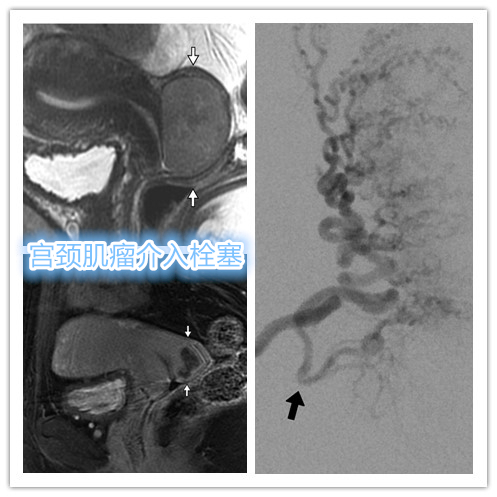

宫颈肌瘤

位于子宫颈的子宫平滑肌瘤很少见,占所有子宫平滑肌瘤的0.9%~8%。 因宫颈部肌瘤同时存在子宫动脉分支及阴道动脉分支参与供血,另血管更为细小,导致肌瘤栓塞后坏死不完全。另有担心异位栓塞导致阴道组织缺血坏死风险。

宫颈肌瘤介入栓塞前后MRI对比

随介入技术水平不断提升,只要术者详细阅读相关影像检查资料,术中精细操作寻找宫颈肌瘤供血动脉,使用较小栓塞剂(PVA-100)进行精细栓塞,亦可达到满意疗效。